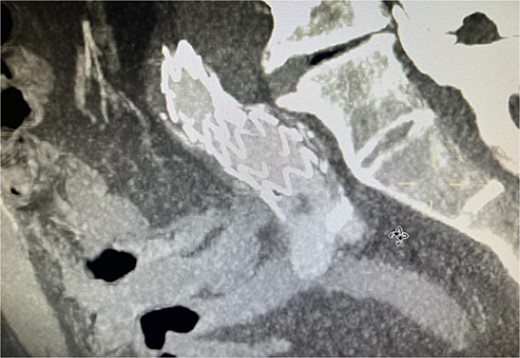

The patient presented 2 months after the initial procedure to the emergency department with burning pain and pallor in his right leg. On physical examination, there was pallor below the knee in addition to loss of pulsation. Physical examination revealed loss of pulsation below the knee. CT angiography (CTA) showed total occlusion of the popliteal artery without any endoleaks, prompting an urgent transpopliteal embolectomy. Trans-esophageal Echocardiography and CTA of the aorta were performed to rule out other sources of embolization, revealing a thrombus adherent to the wall distal to the stent graft (Fig. 3). The patient was started on warfarin.

CTA scan showing the floating thrombus distal to the right iliac artery stent, following the patient presenting with acute embolic ischemia in the right leg.